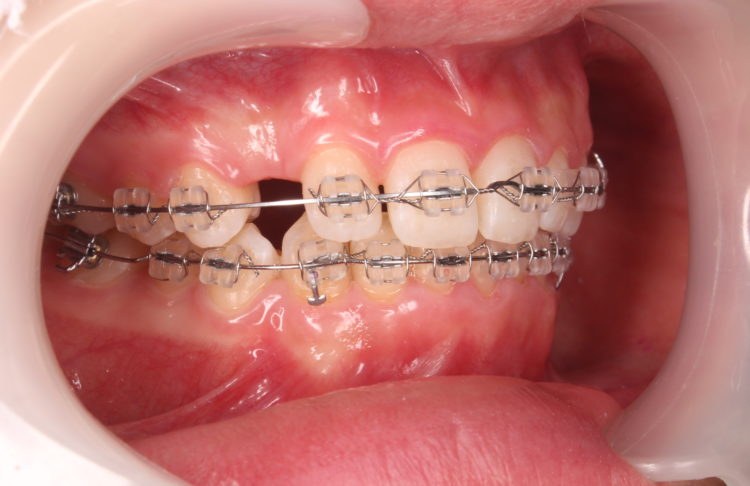

上下の装置が付いた状態です。

ミラー側方観(右側)

だいぶ上顎前歯が圧下され、下の前歯とのスペースが出来てきたので、矯正装置を装着しました。

ここから下顎前歯も圧下(下方に押し下げる)を開始し、歯軸(歯の傾き)等の改善も行っていきます。